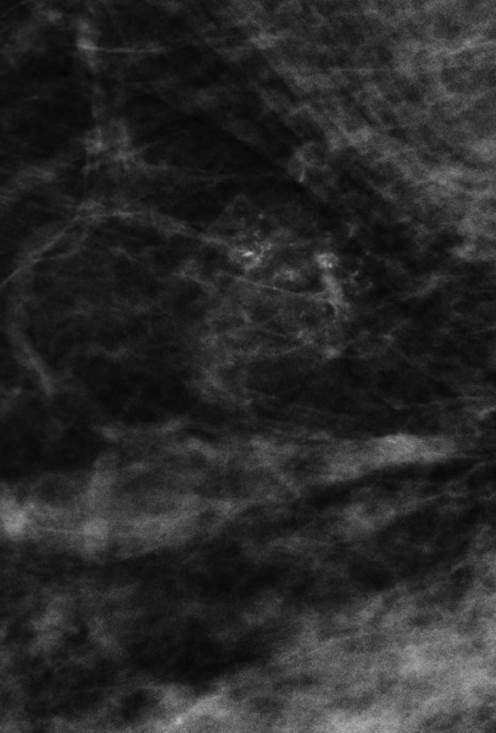

Ung thư vú

Ung thư vú - Ảnh 3

» Thông tin: Nữ giới – 41 tuổi.

» Lâm sàng: Khối tuyến vú.